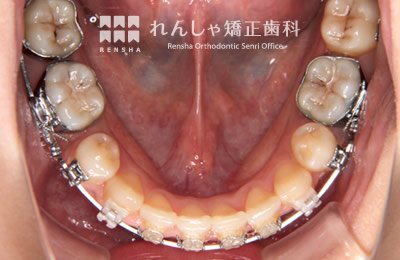

永久歯列はほぼ完成してしますが、歯列を側方だけでなく後方へも拡大し、埋まっていた右上奥歯を引っ張り出しています。

| 主訴 | 埋まったままでてこない歯がある |

|---|---|

| 診断名 | Angle Class II 小臼歯の埋伏と叢生を伴う上顎前突 |

| 初診時年齢 | 13歳5か月 |

| 装置名 | マルチブラケット装置 |

| 抜歯非抜歯 | 非抜歯 |

| 治療期間 | 2年3か月 |

| 費用の目安 | 約82万円+消費税(検査料金、都度の処置費用等も合わせた総額) |

| リスク副作用 | 歯の移動に伴う軽微な歯根吸収、歯槽骨吸収、歯肉退縮(本症例では軽度の歯根吸収を認めた)、矯正器具装着中のカリエスリスク増大(本症例ではカリエス発生無し) |